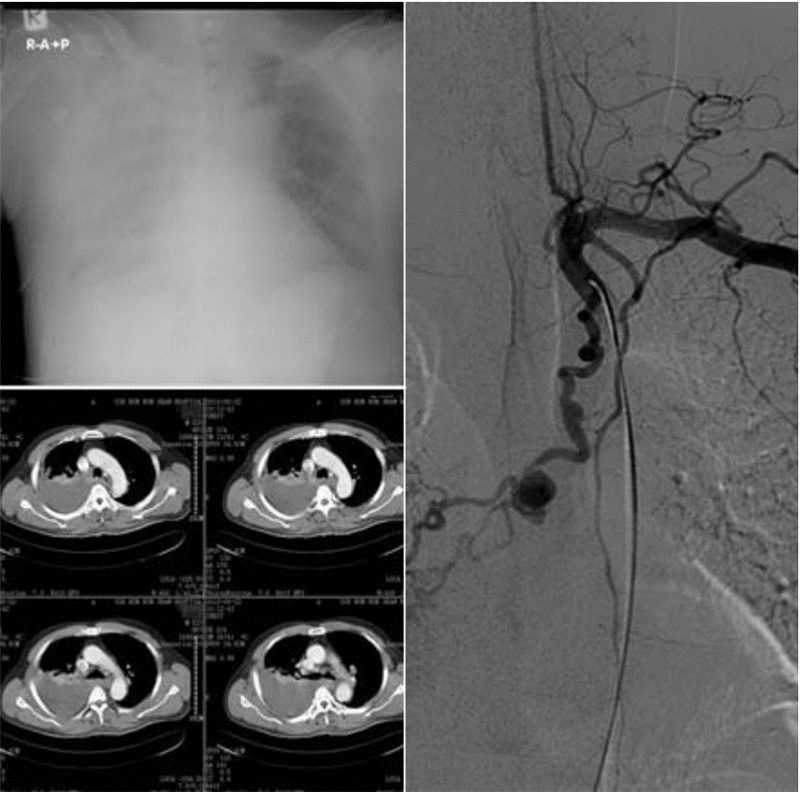

1 资料与方法患者,男性,52岁。因“突发右侧胸痛伴头痛1 d”急诊入院。查体:体温37.2 ℃,心率106次/min,呼吸20次/min,血压147/92 mmHg(1 mmHg=0.133 kPa)。神清,精神软,聋哑,双侧瞳孔等大等圆,光反应灵敏,颈静脉不充盈,气管居中,左肺及右上肺呼吸音清,右中下肺呼吸音消失,叩诊呈浊音,未闻及干湿啰音。心律齐,无杂音,腹平软,无压痛,双下肢无水肿。否认高血压、糖尿病、冠心病史;否认肺结核、支气管扩张征病史;否认药物食物过敏史;否认外伤手术史。血常规:白细胞计数10.4×109 L-1,血红蛋白13.5 g/dL,血小板计数173×109 L-1,中性粒百分数86.5% ;生化提示:电解质、肝肾功能及心肌酶谱正常;凝血功能提示正常。增强CT提示:(1)右肺广泛渗出改变,右下肺部分实变;左肺舌段少许炎症灶;(2)右侧胸腔积液。(3)气管隆突下结节状强化明显,旁边小血管影;后纵隔软组织肿块片,考虑血肿破入右侧胸腔可能(图 1)。立即急诊行主动脉造影+异位支气管动脉(假性动脉瘤)栓塞术,术中见主动脉造影见左侧锁骨下动脉发出异位支气管动脉,异位支气管动脉增粗,于隆突水平呈囊袋样扩张,给予栓塞治疗。术中用5F Cobra导管及微导管超选至异位支气管动脉内,先注入明胶海绵约一片,造影示异位支气管动脉末梢分支消失,但假性动脉瘤仍可显示,然后经微导管释放宝塔型弹簧钢圈2 mm~6 cm×1个,4 mm~8 cm×1个,术后造影示异位支气管动脉闭塞,假性动脉瘤未见显影。介入栓塞后再行右侧胸腔闭式引流治疗。术后恢复良好,第9天出院。术后22 d复查胸部增强CT,异位支气管动脉栓塞术后改变,血栓形成,未见强化影(图 2)。

![]() |

| 图 1 术前胸片、胸部增强CT及术中造影检查 |